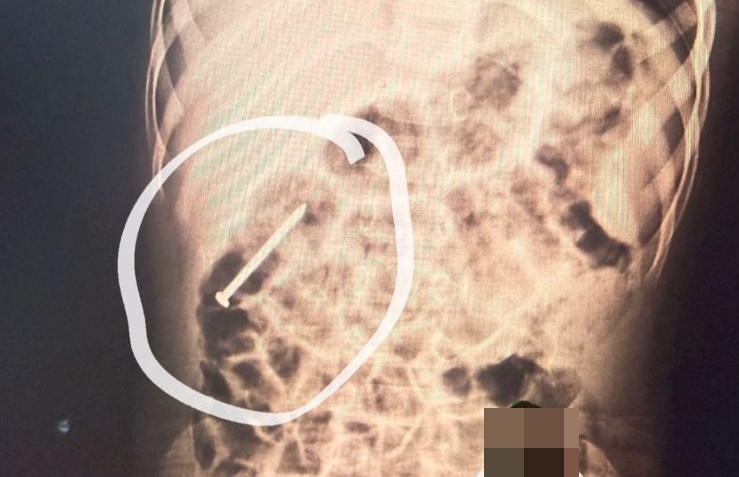

Uma criança de dois anos, moradora do município de Ipixuna, segue internada no Hospital do Juruá após ingerir acidentalmente um prego há aproximadamente seis dias.

O caso continua sendo acompanhado de perto pela equipe médica para garantir a segurança do paciente: Foto/Reprodução

De acordo com a equipe médica, o objeto metálico está percorrendo o sistema digestivo de forma espontânea. Como medida preventiva, o menino permanece sob observação hospitalar enquanto os profissionais aguardam a eliminação natural do material, sem a necessidade de intervenção cirúrgica ou procedimentos invasivos.

Ainda segundo os profissionais de saúde, o quadro clínico da criança é estável e ela apresenta boa evolução. O caso continua sendo acompanhado de perto pela equipe médica para garantir a segurança do paciente.